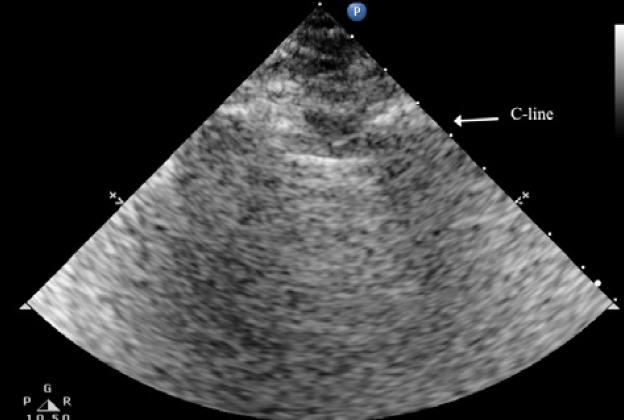

Limited evidence exists to assess the sensitivity, specificity, and accuracy of point-of-care lung ultrasound (LUS) across all age groups. This review aimed to investigate the benefits of point-of-care LUS for the early diagnosis of pneumonia compared to traditional chest X-rays (CXR) in a subgroup analysis including pediatric, adult, and geriatric populations.

The search, conducted across PubMed, Google Scholar, and Cochrane Library databases by two independent investigators, initially identified 1045 articles. Following screening processes, 12 studies comprised a sample size of 2897. LUS demonstrated a likelihood ratio of 5.09, a specificity of 81.91%, and a sensitivity of 92.13% in detecting pneumonia in pediatric, adult, and geriatric patients, with a p-value of 0.0002 and a 95% confidence interval, indicating diagnostic accuracy ranging from 84.07% to 96.29% when compared directly to CXR.

Our review supports that LUS can play a valuable role in detecting pneumonia early with high sensitivity, specificity, and diagnostic accuracy across diverse patient demographics, including pediatric, adult, and geriatric populations. Since it overcomes most of the limitations of CXR and other diagnostic modalities, it can be utilized as a diagnostic tool for pneumonia for all age groups as it is a safe, readily available, and cost-effective modality that can be utilized in an emergency department, intensive care units, wards, and clinics by trained respiratory care professionals.